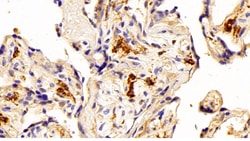

IBA1 Polyclonal Antibody for Western Blot, IHC (P)

Ionized calcium-binding adapter molecule 1 (IBA1), also known by its gene name AIF1, is a protein expressed predominantly by microglia in the brain and spinal cord. This protein belongs to the EF-hand calcium-binding protein family and plays a crucial role in microglial activation and migration in response to brain injury or neuroinflammation. IBA1's function is integral to microglial motility and phagocytic activity, facilitating the cellular response to pathogenic stimuli and promoting tissue homeostasis and repair in the central nervous system. IBA1 serves as a reliable marker for activated microglia in various neurological disorders, including Alzheimer's disease, Parkinson's disease, and multiple sclerosis, where increased expression correlates with disease progression and severity. The protein's structural features enable it to bind calcium ions, inducing conformational changes that activate signaling pathways essential for microglial function. Its expression is highly regulated by inflammatory cytokines, underpinning its role in neuroimmune responses. Due to its specific expression in microglia during pathological conditions, IBA1 is widely used in research as a marker to study microglial status and activity, and it remains a focal point for understanding microglial involvement in neurodegenerative diseases.Specifications

| Immunohistochemistry (Paraffin), Western Blot | |